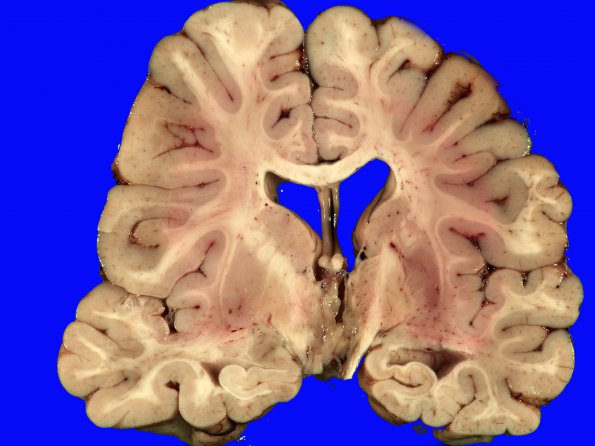

The suprasellar parenchyma lining the third ventricle appears gray, somewhat soft and gelatinous, and has focal chalky areas consistent with calcifications.